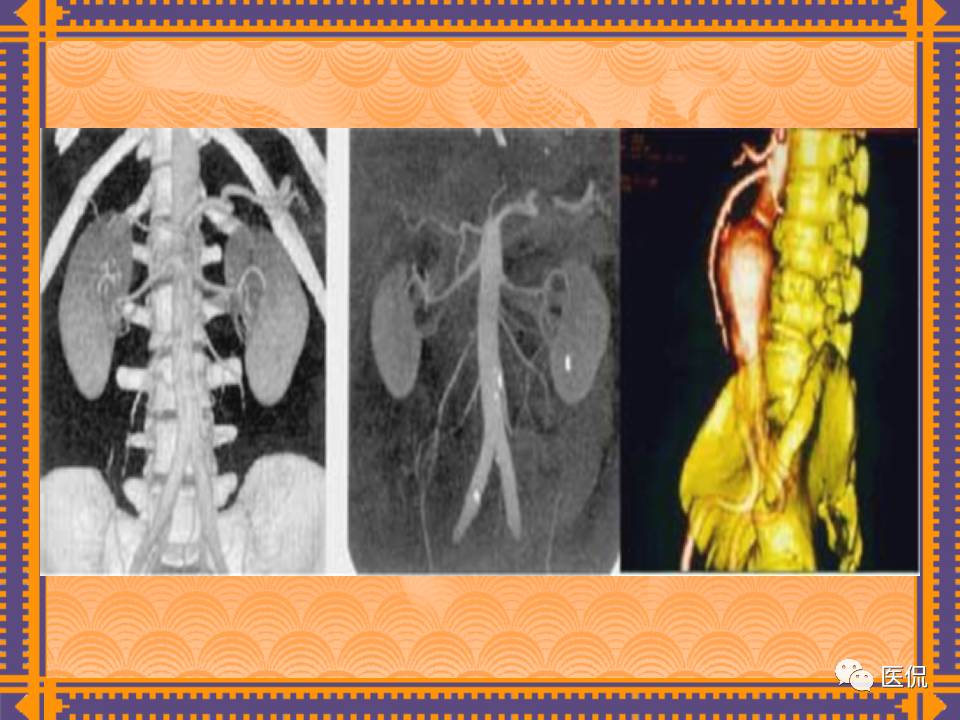

这篇PPT对男性生殖系统疾病:前列腺增生、前列腺癌;女性生殖系统疾病:子宫肌瘤、子宫癌、卵巢囊肿和卵巢肿瘤以及腹膜后间隙疾病进行了详细讲解。